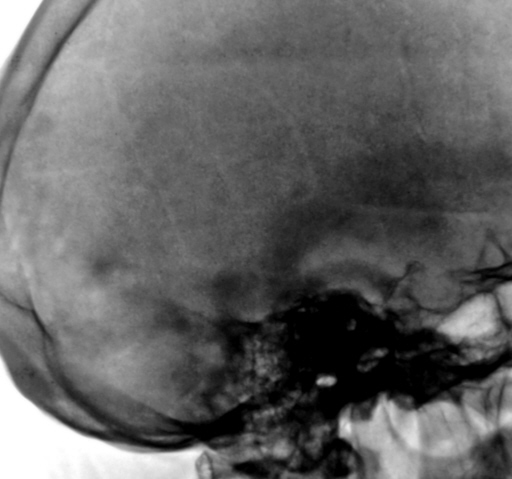

Представлены, на диске, такие изображения черепа. Что посоветуете уважаемые коллеги?

Уважаемый  Валентин Львович, я так понимаю Вас смущает ячейки лобной пазухи? В данном случае надо обратить внимание на толщину костей крыши черепа, а следовательно и на турецкое седло, следует проконсультироваться у эндокринолога с дальнейшим проведением МР-исследования гипофиза.

По моему у Ясиновской когда -то читал, что гиперпневматизация пазух - косвенный признак эндокринной патологии, а так ничего настораживающего.

Структура затылочной кости не совсем обычная...похоже на "пробойниковые отверствия"...касаемо лобных пазух - такой "фасон", мне кажется это природа, и мало вероятно, что ендокринология...

Кости свода толстоваты, пазухи крупные. Турецкое седло не изменено. По-моему, стоит беспокоиться, только если есть эндокринные нарушения.

Файзуллин, если мне не изменяет память, частенько, гиперпневматизацию пазух связывал с опухолевым ростом. Но в данном случае, по всей видимости, вариант или аномалия развития лобной пазухи.